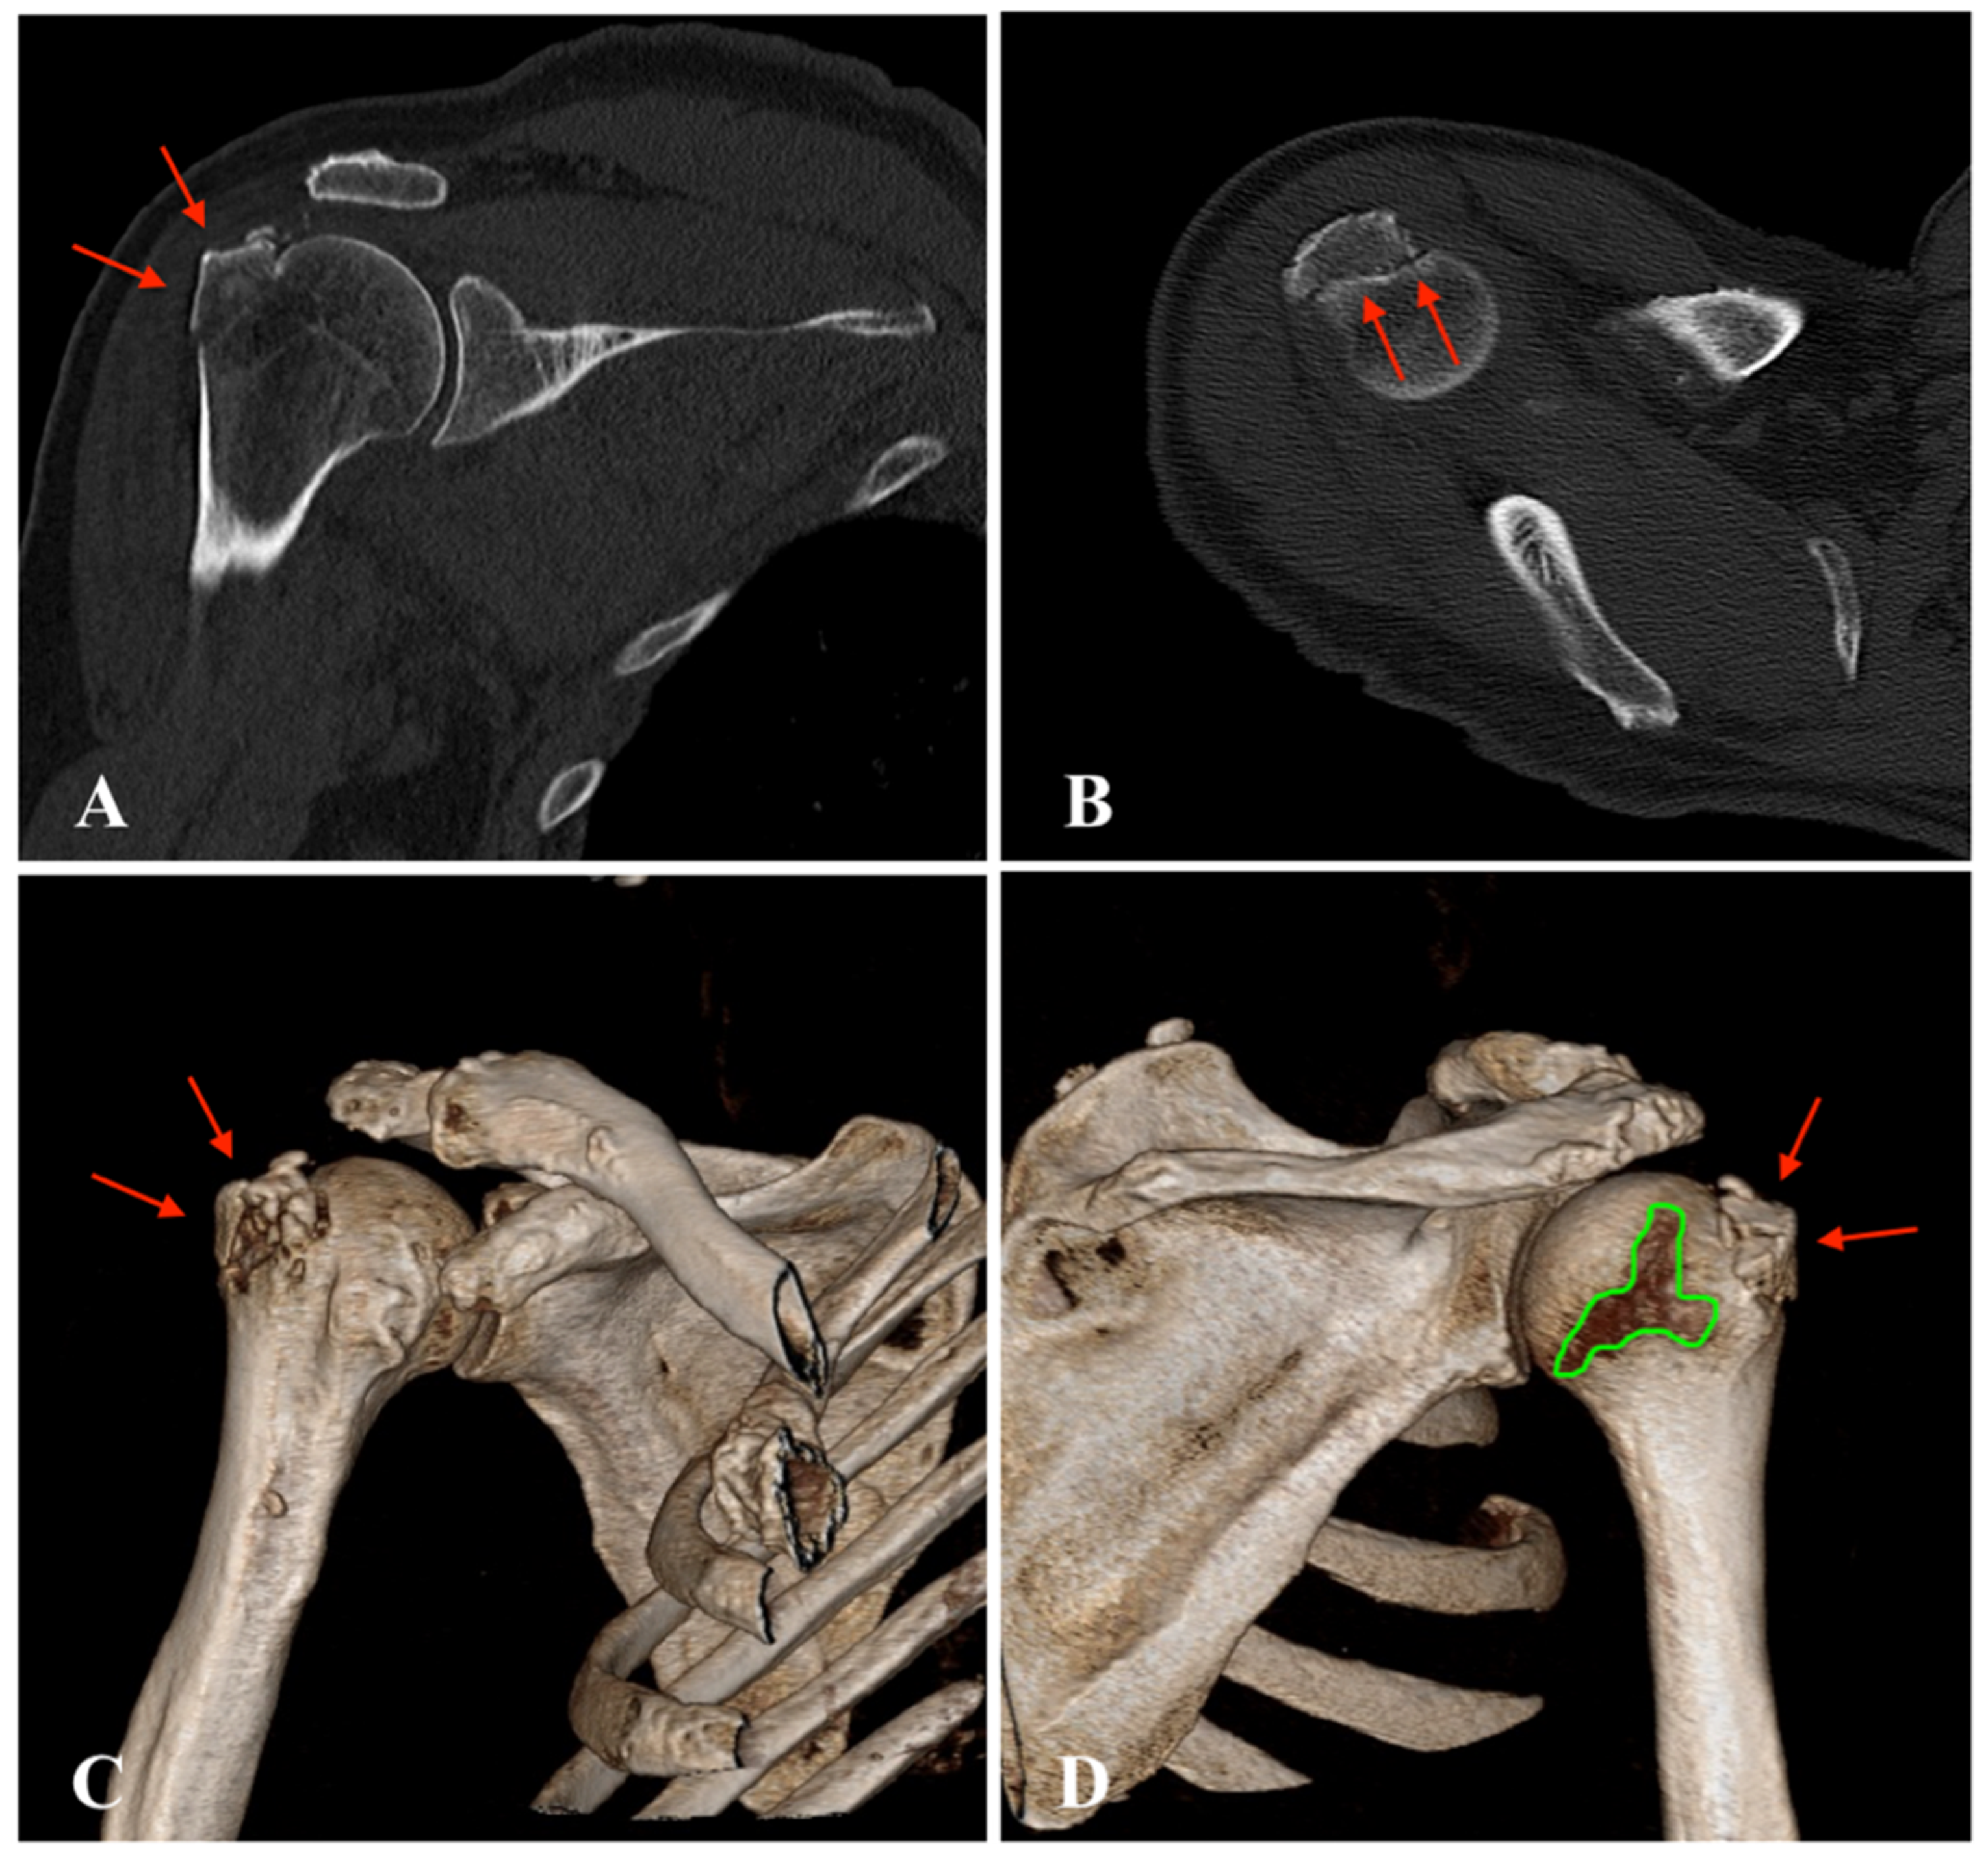

| 2 | - Bony Bankart lesion - Greater tuberosity fracture - Hill-Sachs lesion | None | Bony Bankart lesion | None | Arthroscopic Bankart repair |